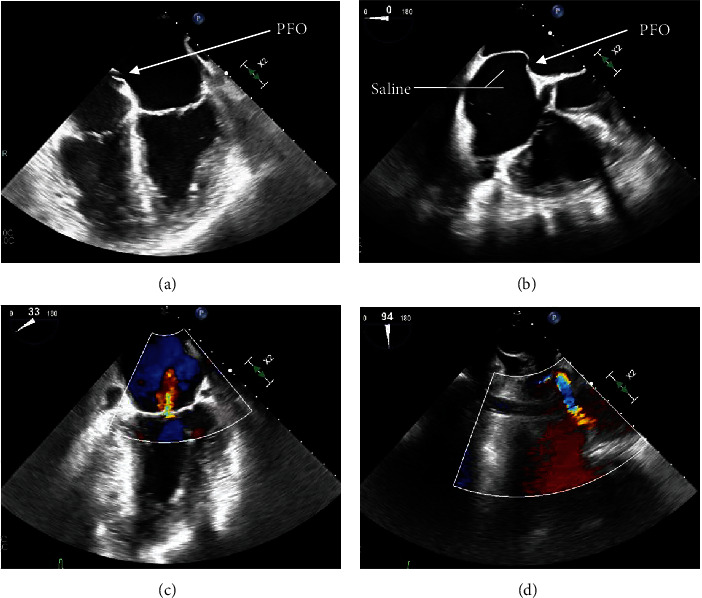

A 67-year-old woman with pulmonary hypertension (PH) presented with a 1-day history of worsening shortness of breath and pleuritic chest pain and was found to have a troponin T level of 3755 ng/L (ref. range 0-19 ng/L). An initial diagnostic workup in the emergency department (ED) led to an urgent left heart catheterization which revealed a 90% occlusive right coronary artery blood clot, even though a recent heart catheterization less than a month prior was completely unremarkable. Further workup led to the discovery of a patent foramen ovale (PFO) and an aneurysmal interatrial septum, suggesting the presence of a paradoxical embolism. While typically asymptomatic, a PFO is an important clinical entity that can lead to irreversible cardiac damage. Suspicion should be high for this finding in the case of an acute myocardial infarction (MI) with no clear cause, especially in a patient with elevated right heart pressures.